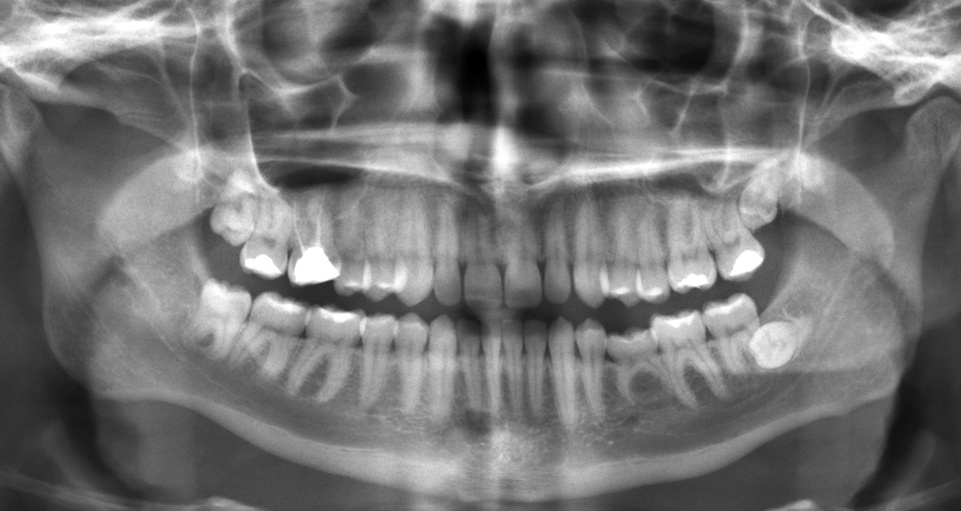

Phim X-quang nha khoa giúp bác sĩ thấy hình ảnh về mô cứng (răng và xương) và mô mềm bao quanh các răng, xương hàm. Cụ thể hơn, phim X-quang tạo điều kiện để bác sĩ nhận biết được các bệnh lý sau:

- Sâu răng (trong thân răng hay sâu răng dưới phục hình, miếng trám).

- Bệnh lý của xương hàm.

- Bệnh nha viêm chu (nướu).

- Các nhiễm trùng tiến triển dưới nướu.

- Các u vùng hàm mặt.

| Có thể thấy được rất nhiều điều từ một phim X-quang nha khoa. |